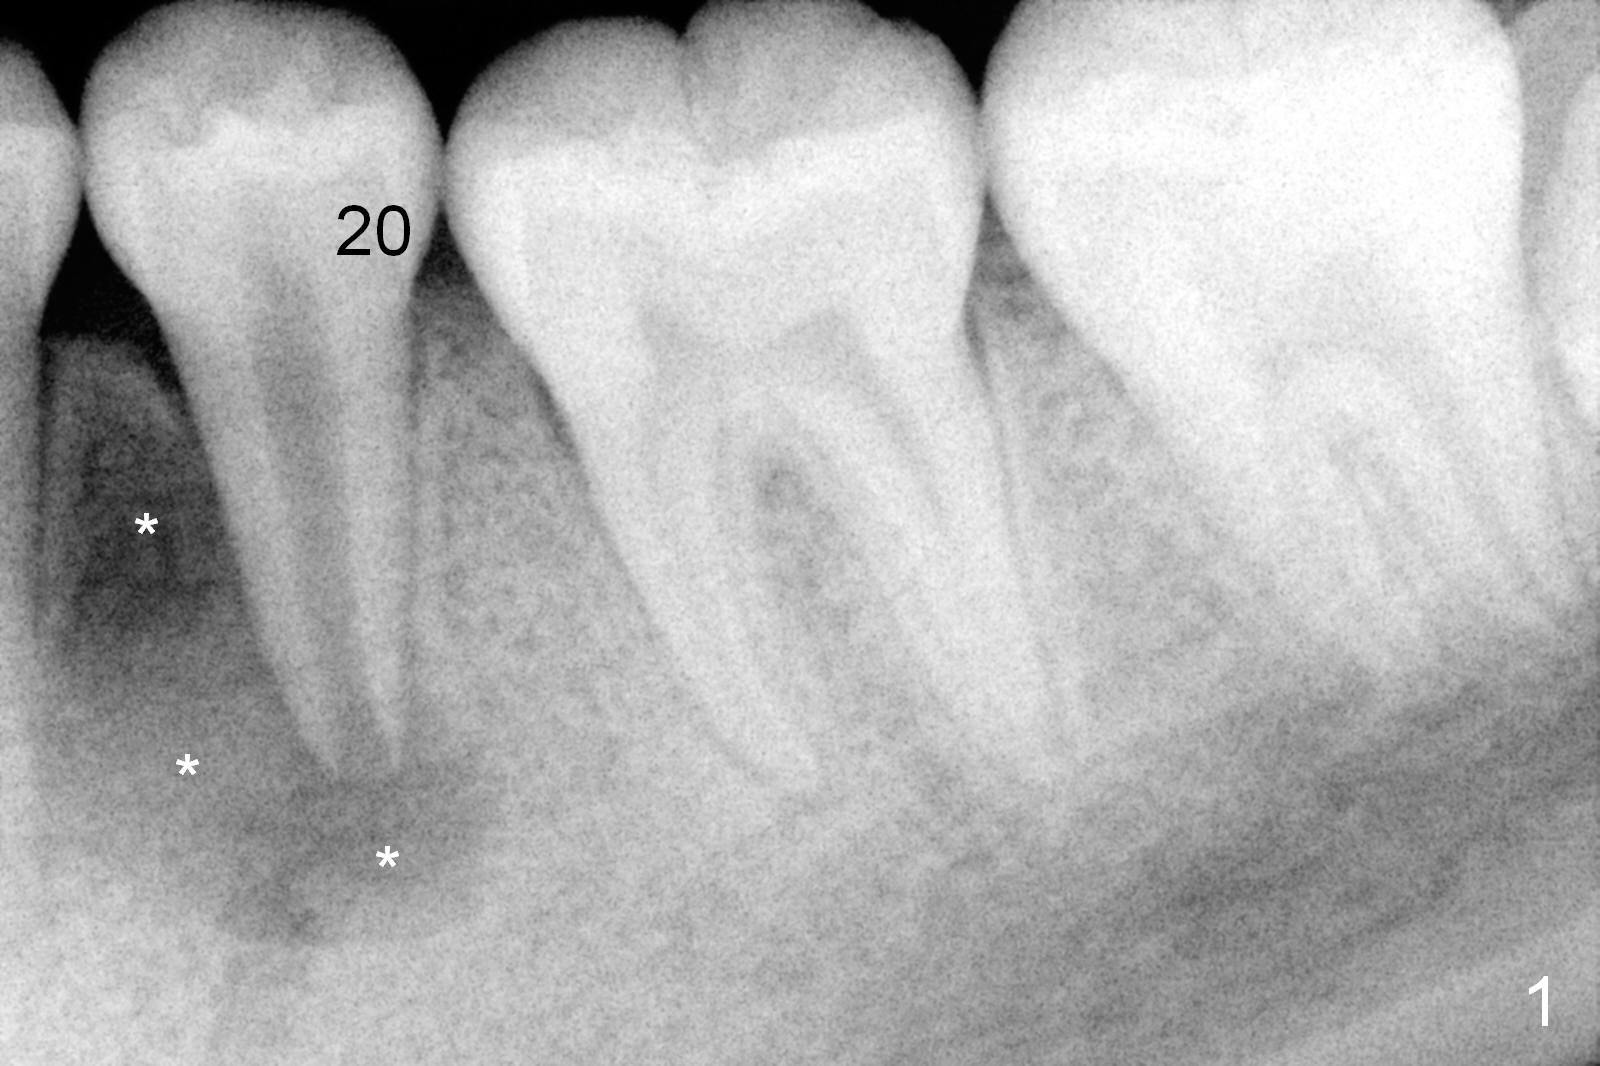

A 13-year-old girl has a buccal apical fistula at the tooth #20 with large periradicular radiolucency (Fig.1 *). After canal debridement, calcium hydroxide paste is placed in the canal (Fig.2 *). One month later, the fistula does not disappear with light percussion. New paste is placed (Fig.3). Two months later, the fistula disappears without percussion. The existing paste (Fig.4) is changed (Fig.5 (yellow: radiolucency; red: Inferior Alveolar Canal)). Another 2 months later, the fistula does not recur; as before, the paste density decreases, so does periradicular radiolucency (Fig.6). Root canal is packed (Fig.7). Six months postop, periradicular radiolucency continues to decrease, while the lamina dura at the apex is discontinuous (Fig.8 between arrowheads). Seven years postop, the lamina dura at the apex is seemingly intact (Fig.9). The patient remains asymptomatic at #20. In fact there is an acute infection at #29.